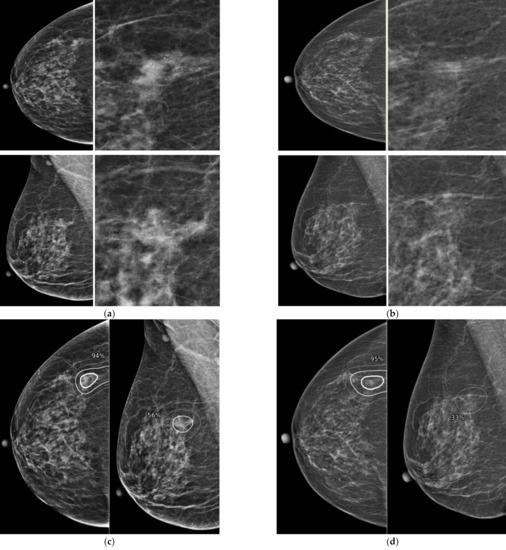

Figure 3.

Representative dismissed case by AI-CAD. A 62-year-old woman classified as negative in a mammography screening (a). When looking at the mammography in retrospect, asymmetry only seen in MLO view was newly developed in the upper and posterior aspect of right breast. This lesion was missed in the prior mammogram. When analyzed retrospectively, AI did not recognize this lesion either. (b) After 18 months of diagnostic mammogram, the previous asymmetry became a spiculated mass and a biopsy confirmed it as invasive cancer.